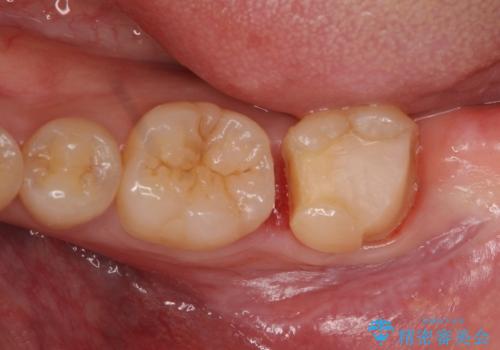

他院で入れたセラミックインレーが取れた。

- 他院で入れたセラミックの詰め物が取れてしまい来院。

適合を確認したところ、不適合だったため新しく形を作り直して、型取りをした方が良いことを説明した。

セラミックの詰め物で治療すると、詰め物の範囲が大きくなり、割れてしまう可能性があるので以下の治療の提案をした。